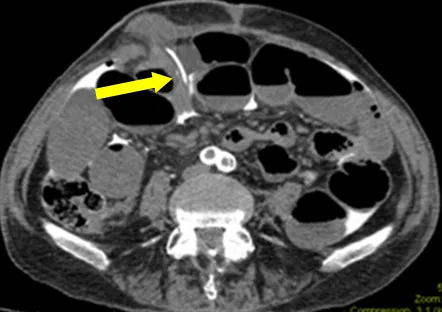

Visual Aid